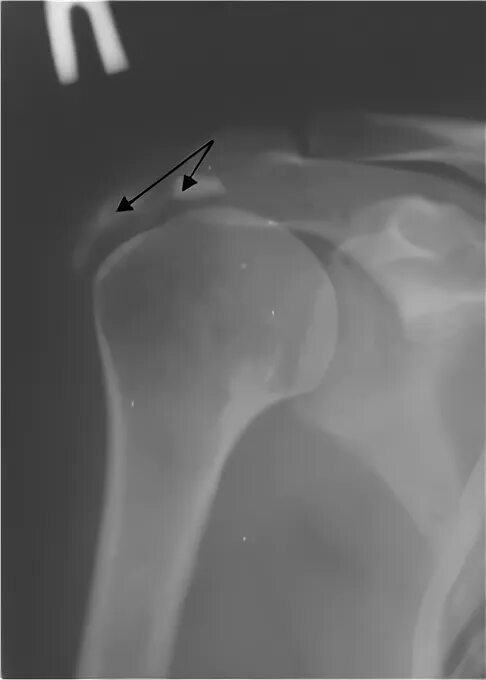

Обызвествление сухожилий мышц